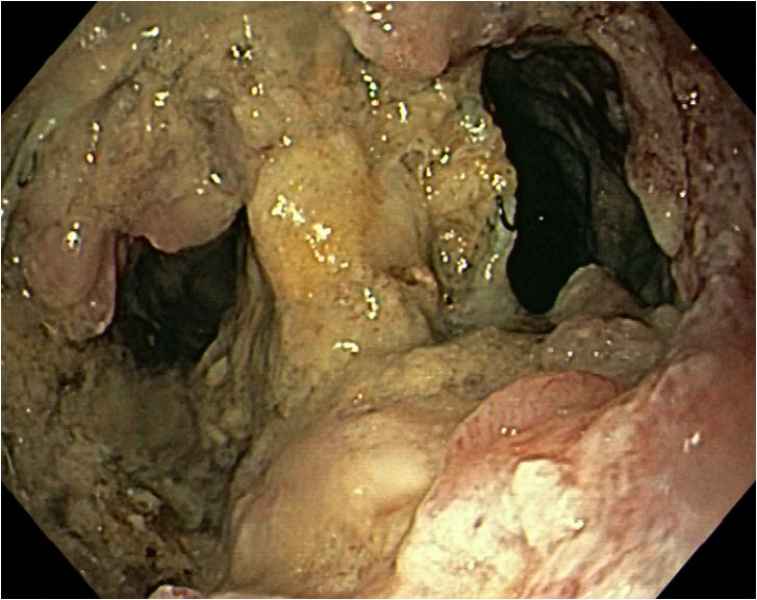

Infinity stones in a choledochocele

Fotografias